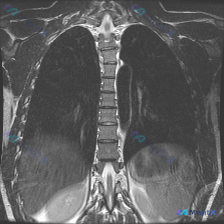

网上看到一份胸部MRI冠状位T2WI的影像资料,结合后续分析觉得挺有意思的,放出来大家一起讨论。 先把看到的信息整理一下: - 影像核心发现:双侧下肺野/膈顶部T2高信号,呈典型“半月征”,符合双侧胸腔积液;纵隔居中,无明显肿大淋巴结,肺野内没看到明确实变或占位,胸壁软组织、肋骨及胸椎骨髓信号看起来...